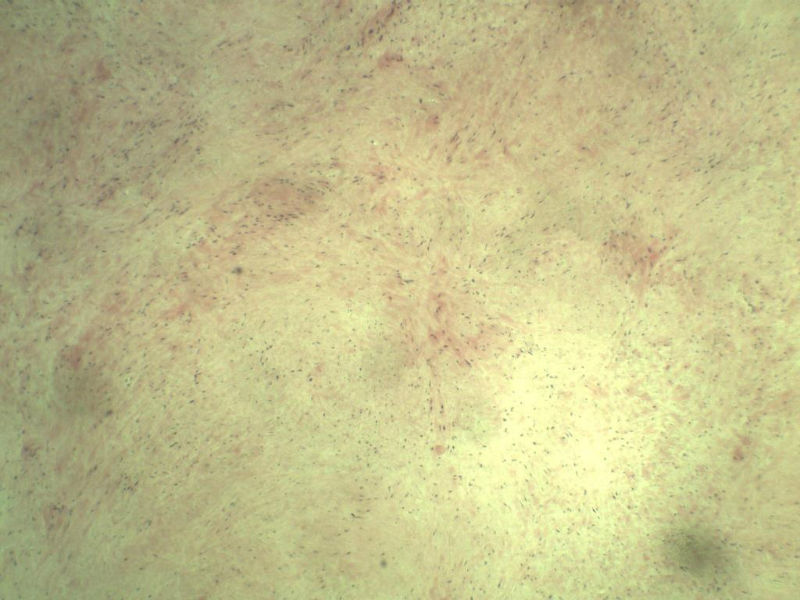

男,51岁, 4月前患者无意中发现右腘窝一包块,约核仁大小无疼痛, 4月来包块进行性生长

灰褐类圆形包块一个,直径 5 cm,切面灰白,实性,编织状。 请各位老师看看 是什么? 谢谢!